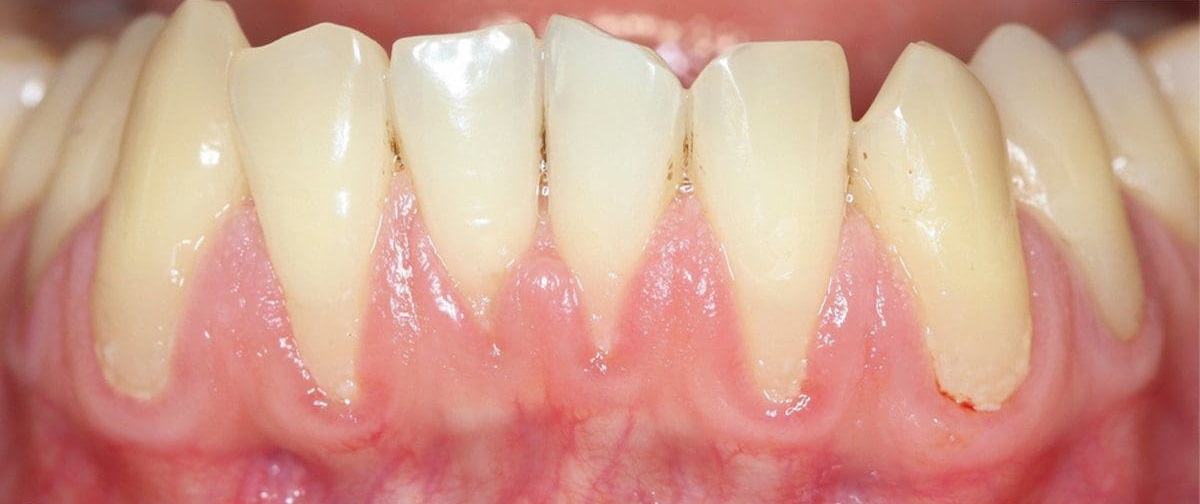

Chân răng là phần neo giữ răng trong xương hàm. Nếu chân răng ngắn bẩm sinh hoặc hình thể dị dạng, khả năng chịu lực sẽ kém hơn rất nhiều. Bất kỳ ca niềng răng nào cũng sẽ có một mức độ tiêu chân răng sinh lý nhất định (khoảng 1-2mm). Với người có chân răng dài, điều này không đáng ngại. Nhưng với người chân răng vốn đã ngắn, việc mất thêm vài milimet có thể khiến tỷ lệ thân răng/chân răng mất cân đối nghiêm trọng, dẫn đến răng bị lung lay sớm.

Khách hàng gặp các vấn đề về chân răng cũng nên cân nhắc và thăm khám kỹ trước khi niềng

Bác sĩ phải kiểm soát được lực tác động lên răng để không làm tiêu thêm chân răng. Trong quá trình niềng, bác sĩ phải sử dụng lực cực kỳ nhẹ nhàng và liên tục kiểm tra bằng phim X-quang mỗi 3 - 6 tháng. Nếu phát hiện tiêu chân răng tiến triển, bác sĩ buộc phải tạm dừng lực hoặc kết thúc điều trị sớm hơn dự kiến để bảo tồn răng thật cho khách hàng.